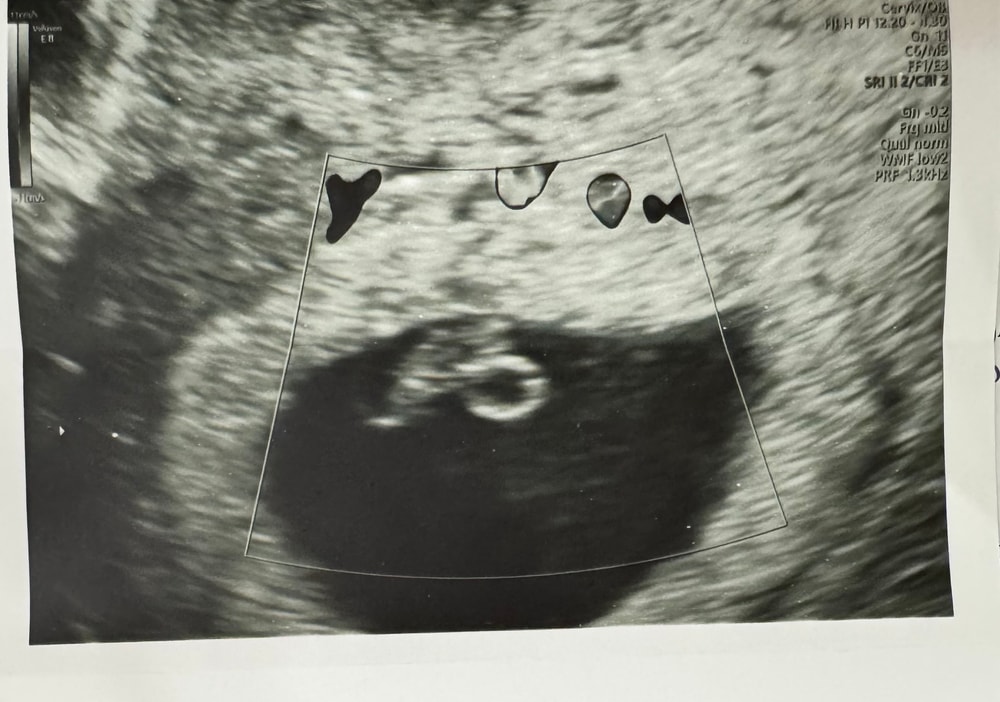

Замершая 6.6 недель

Замершая и внематочная беременностьСегодня 30ДПП и я бежала к Ре слушать сердечко… сердцебиения нет, проверили на другом аппарате, 2 врача подтвердили замершую.

ВДПЯ - 25.93

КТР - 8.55

ЖМ - 4.96